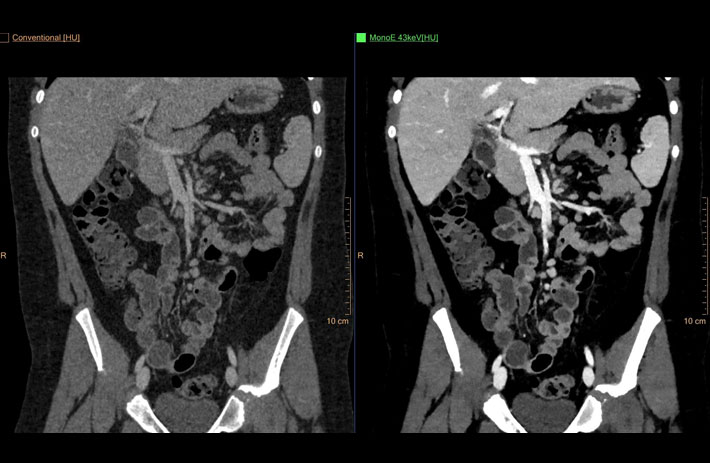

Mit dem Spektral-Detektor-CT werden Spektraldaten automatisch bei jedem Scan erfasst. Die Informationen stehen jederzeit auf der Scankonsole, der CT-Workstation sowie an jedem PACS-Arbeitsplatz zur Verfügung, sodass es nicht notwendig ist, den Patienten erneut zu scannen, bspw. wenn initial zufällige Anomalien festgestellt wurden. Dadurch profitieren Anwender durch eine höhere Diagnosesicherheit und weniger Nachuntersuchungen auf anderen bildgebenden Systemen. Unsere Fallsammlung zeigt, welchen klinischen Mehrwert der Spektral-Detektor-CT in unterschiedlichsten Anwendungsbereichen in der klinischen Routine bringt. Jede Woche gehen neue Fälle live.